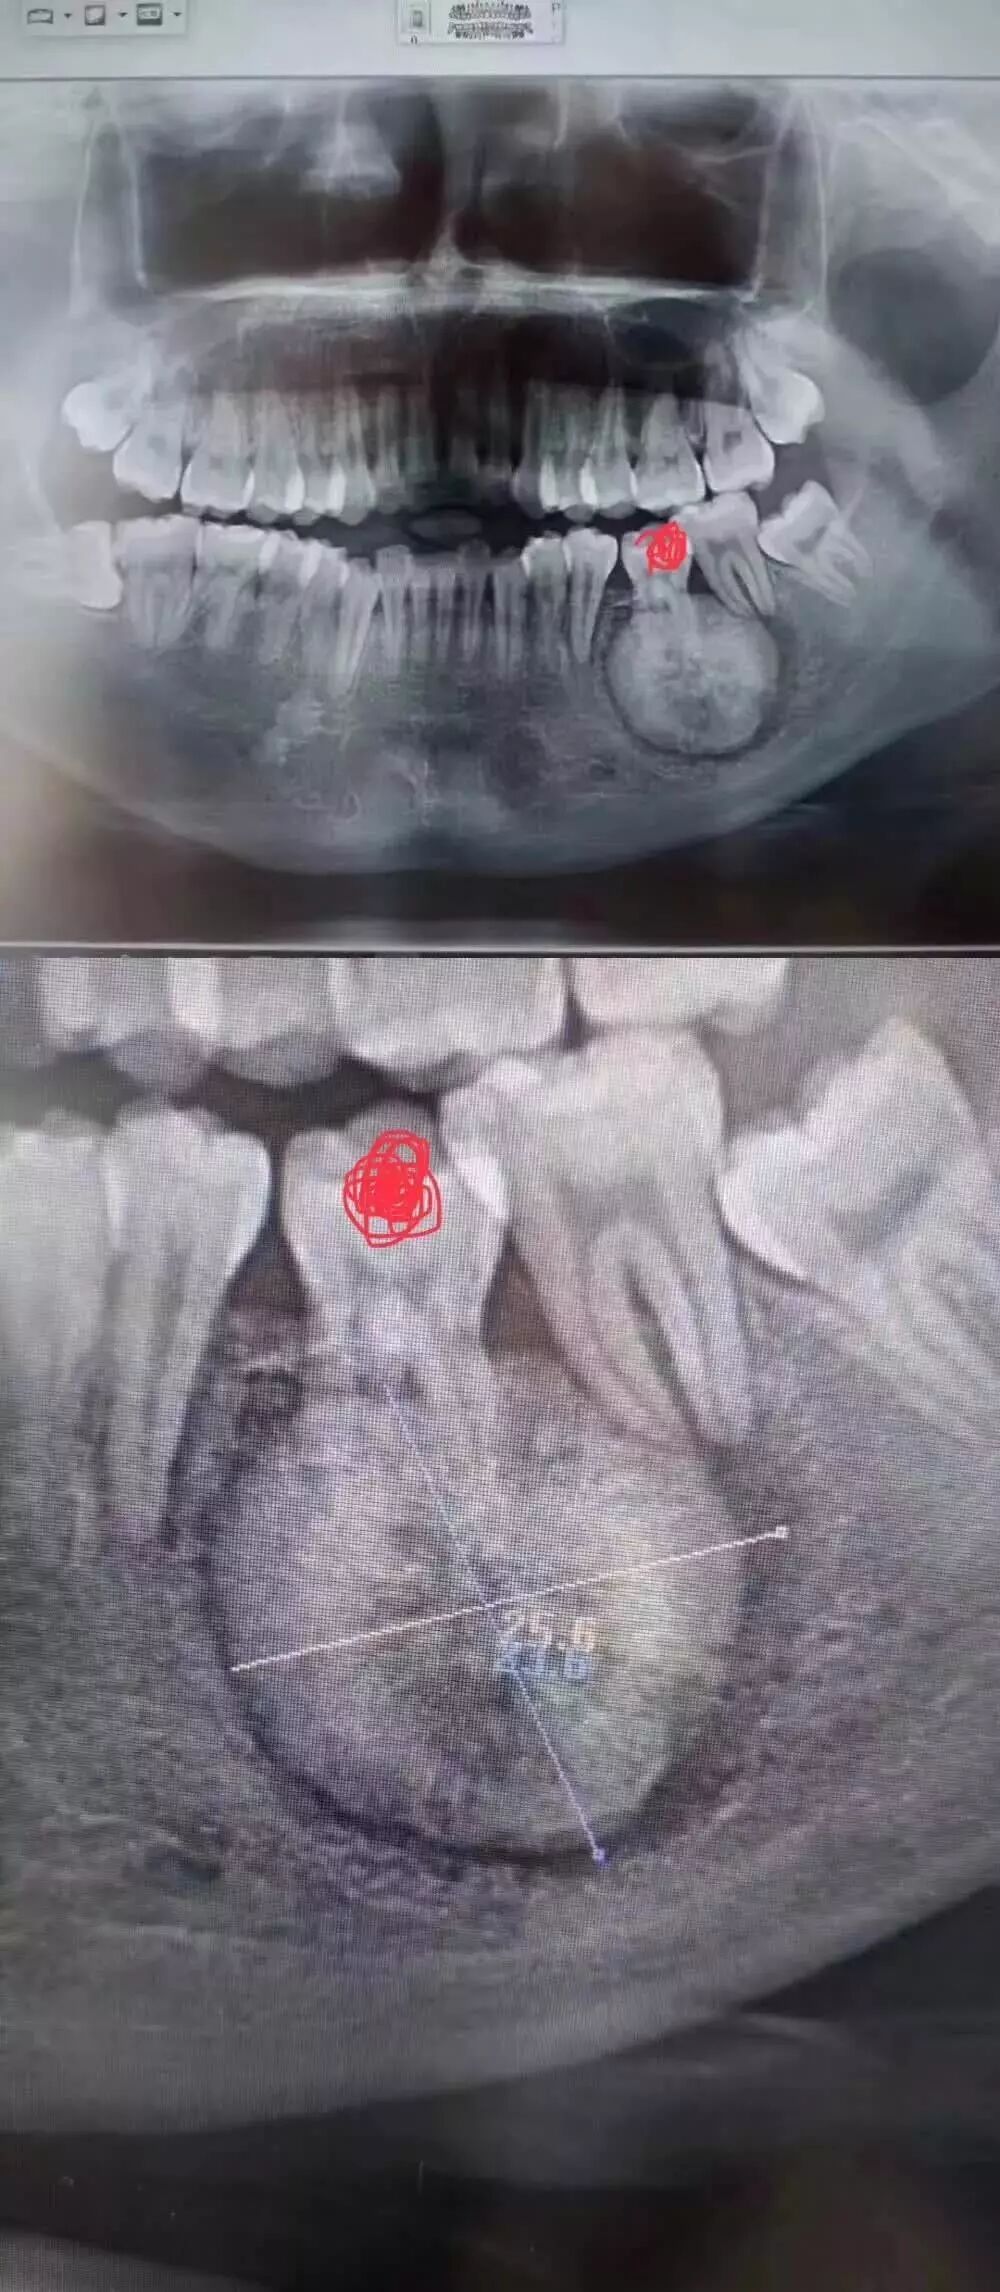

周末,小温不经意间发现一个拔牙案例刷爆了牙医们的朋友圈

相信大部分的人和小编一样,没等看到具体病情就已经被图中这个巨大的“球”状物体吓到。小小的下巴竟能长出这么大的“球”!

“患者是30多岁的年轻男子,红色标记那颗牙松动,要求拔牙,开始嫌麻烦不愿拍片,后来经过再三劝说还是拍了片。

结果把所有人包括他自己都吓了一跳。

估计是良性,具体还得去医院住院手术做病理检查,所以大家不要忽视一张片子带来辅助检查的重要性。”

试想,如果没有拍片,直接贸然拔牙,一旦出现问题......

一张牙片,“救了”诊所,也“救了”患者!